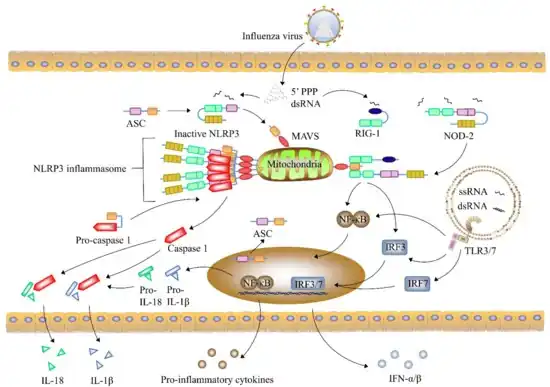

Common symptoms of the flu such as fever, headaches, and fatigue are the result of the huge amounts of proinflammatory cytokines and chemokines (such as interferon or tumor necrosis factor) produced from influenza-infected cells.[100][101] In contrast to the rhinovirus that causes the common cold, influenza does cause tissue damage, so symptoms are not entirely due to the inflammatory response.[102] This massive immune response might produce a life-threatening cytokine storm. This effect has been proposed to be the cause of the unusual lethality of both the H5N1 avian influenza,[103] and the 1918 pandemic strain.[104][105] However, another possibility is that these large amounts of cytokines are just a result of the massive levels of viral replication produced by these strains, and the immune response does not itself contribute to the disease.[106] Influenza appears to trigger programmed cell death (apoptosis).[107]